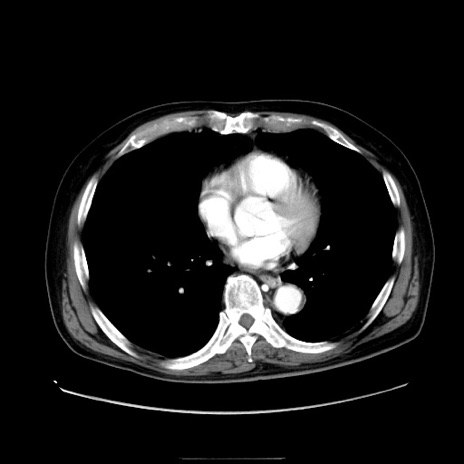

症例30(横断像)

【症例】80歳代男性

【主訴】臍周囲痛

【現病歴】約6時間前から臍下部痛が出現。次第に腹部膨隆・背部痛も生じてきたため来院。背部痛の場所は変化しない。

【身体所見】意識清明、BT 36.3℃、BP  131/87mmHg、P 87bpm、SpO2 100%(RA)、臍周囲自発痛・圧痛あり、反跳痛なし、自発痛部位に一致して板状硬あり、腹部膨隆、腸雑音減弱、CVA tenderness両側陰性。

【データ】WBC 19600、CRP 0.33